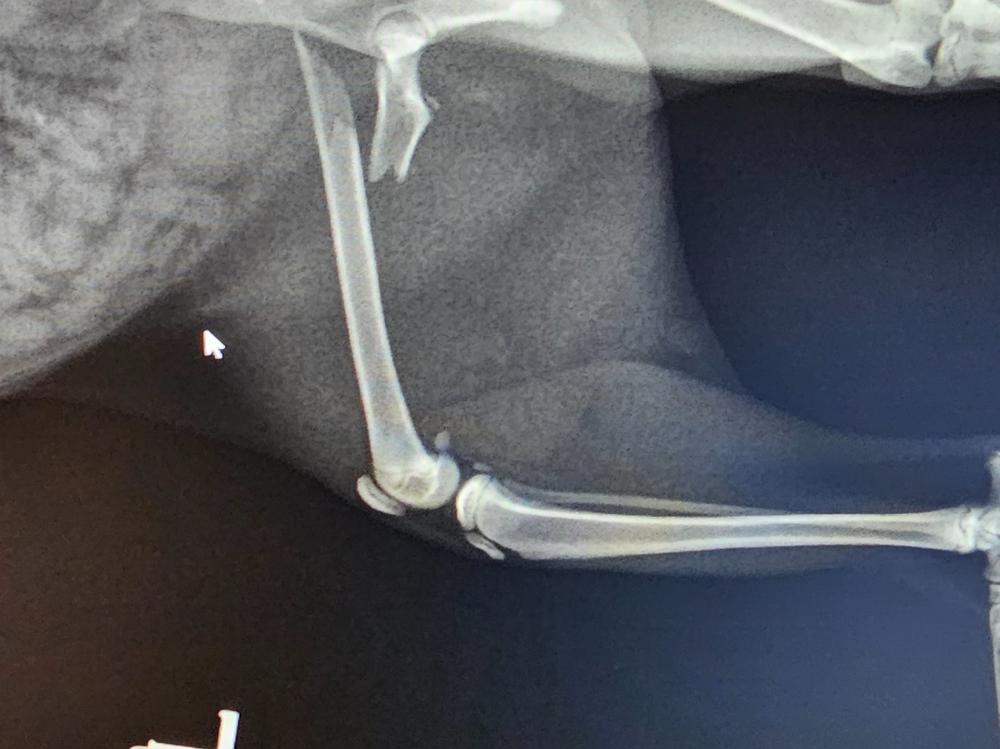

Hammer is 8 months old and just under 2kgs so just a wee mite but she has a big heart and is very adventurous!

It seems our wee buddy has had a fall and now needs surgery to pin her hind left femur back together! For the consult and xrays we have already paid 550 but anything you could help us with towards the $3,000.00 surgery would be greatly appreciated! If we are lucky enough to go over the amount we need we would love to donate to the rescue I foster for as they are fast becoming swamped with new babies too, just in time for Christmas and I am happy to provide proof of doing this.